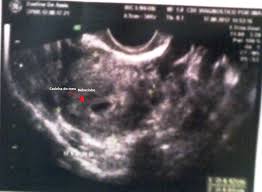

10 a 13 semanas e meia de gestação. Com 5 semanas de gestação o saco gestacional mede em torno de 4 a 16 mm e pode dobrar de tamanho ao decorrer da semana. O seu corpo A complexidade inicial do desenvolvimento humano faz com que as primeiras semanas de gestação sejam as mais críticas da gravidez.

Sua cabeça e seu coração são tão pequenos que um ultrassom nesta fase seria impossível de detectar. O seu coração bate pela primeira vez e a um ritmo duas vezes mais rápido do que o da mãe. Com 5 semanas de gestação o saco gestacional mede em torno de 4 a 16 mm e pode dobrar de tamanho ao decorrer da semana. 5 Semanas de gestação. Minha primeira gestação - 5 semanas About Press Copyright Contact us Creators Advertise Developers Terms Privacy Policy Safety How YouTube works Test new features 2020 Google LLC. 5 Semanas de Gravidez Do 29º dia ao 35º dia de gravidez. Desenvolvimento do bebê - 5 semanas de gestação Desenvolvimento do bebê.